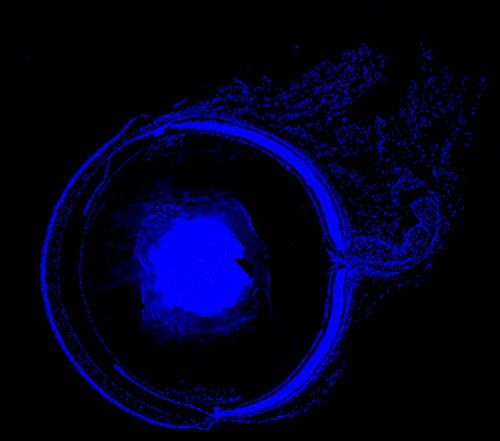

實驗結果展示:

DAPI染色-小鼠眼球